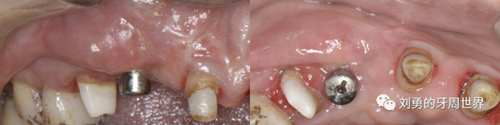

上圖中,種植體唇側(cè)缺乏附著齦,從上腭取瓣,常規(guī)做法:取長而寬的齦瓣,這樣供區(qū)面積大,術(shù)后疼痛重。

為了減少痛感,從雙側(cè)上腭取多條長而窄的齦瓣進(jìn)行移植,這樣每個供區(qū)的傷口都比較窄,可以減少術(shù)后的痛感。

可見右上前牙植體頰側(cè)無附著齦

為了減少取瓣大小,從上腭取厚一點(diǎn)的齦瓣,然后用刀片平行于表皮表面將齦瓣片切成兩個厚度一致的齦瓣,然后進(jìn)行移植,這樣切成的兩個齦瓣一個有表皮,一個沒有表皮是單純的結(jié)締組織。如此的片切可以使齦瓣變成雙倍的大小使用,減少了供區(qū)的取瓣面積。